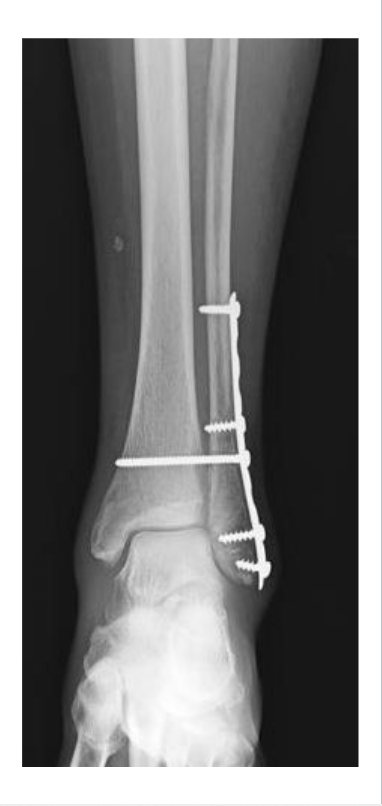

Open Fracture

Definition: Bone breaks through the skin (or skin is broken, exposing bone)

Mechanism: High-energy trauma (ex: motor vehicle accident, gunshot)

Clinical note: High infection risk and delayed healing.

Key concept: Requires surgical cleaning and fixation

<p><strong>Definition:</strong> Bone <strong>breaks through the skin </strong>(or skin is broken, exposing bone)</p><p><strong>Mechanism: High-energy trauma </strong>(ex: motor vehicle accident, gunshot)</p><p><strong>Clinical note: High infection risk and delayed healing.</strong></p><p><strong>Key concept</strong>: Requires surgical cleaning and fixation</p>